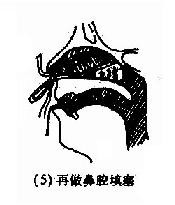

(2)后鼻孔填塞法(postnasal packing):先将凡士林纱条或消毒纱布卷迭成块形或圆锥形,长约3.5cm,直径约2.5cm,用粗线缝紧,两端各有约25cm长的双线,消毒备用。填塞时先收缩和表麻鼻腔粘膜,咽部亦喷有表面麻醉剂。用导尿管由前鼻孔沿鼻腔底部插入直达咽部,用镊子将导管从口腔拉出,导尿管尾端则留于前鼻孔外,再将填塞物上的双线系于导尿管,此时将填塞物由口腔送入鼻咽部,填塞于后鼻孔。为了减少患者痛苦,可用弯止血钳将填塞物在明视下送到悬壅垂的后上方,再将导尿管的鼻端向外拉紧。最后在前鼻孔处用一纱布球,将双线系于其上,以作固定,口腔端的线头可剪短留在口咽部,便于以后取出填塞物时作牵拉之用。后鼻孔填塞后,一般都需加行鼻腔填(图4-7)。鼻腔填塞物应于24~48小时内取出或更换,以防引起鼻窦及中耳感染等并发症。

图4-7 后鼻孔填塞法